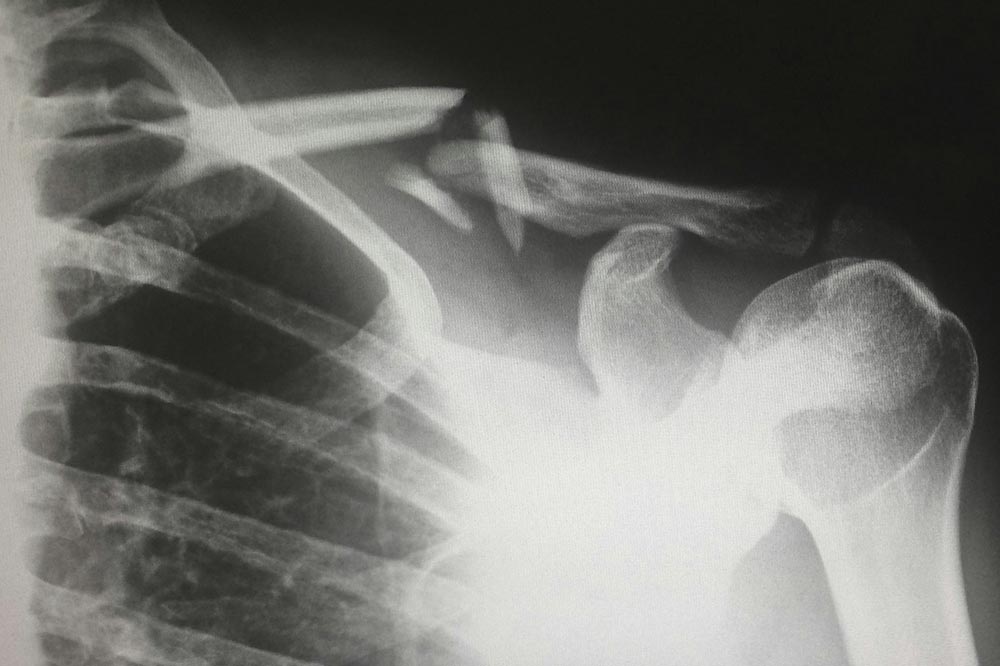

Il complesso della spalla è il più mobile del nostro corpo e ci consente una grandissima libertà di movimento garantita dall’azione in concerto di quattro articolazioni, tra cui quella che nel gergo comune viene chiamata spalla, ovvero la gleno-omerale. Quando si parla di frattura di spalla spesso si fa riferimento alle fratture prossimali di omero […]